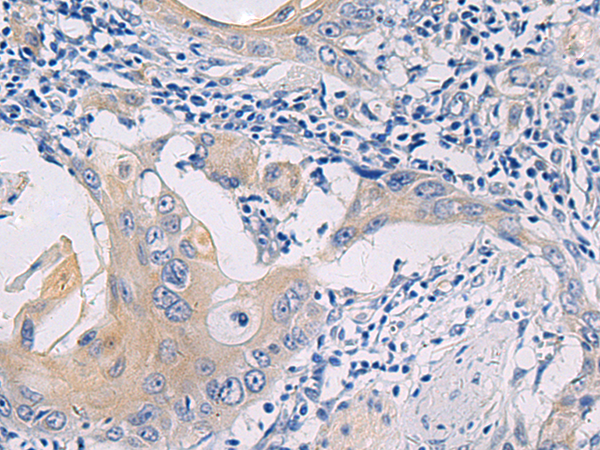

分类: 科研抗体货号: P13458别名: SCN2; GFI-1; GFI1A; ZNF163应用: IHC反应种属: Human, Mouse, Rat